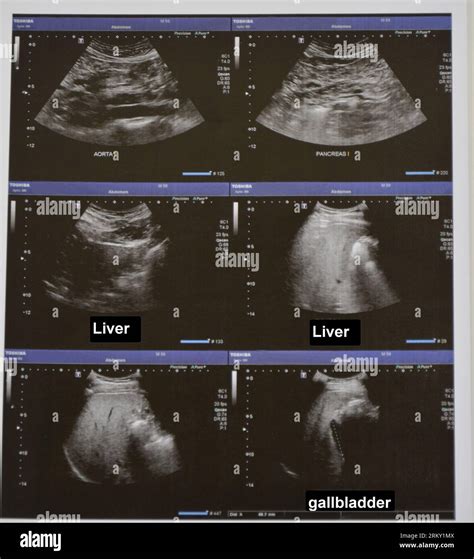

• Liver and Gallbladder: Assessing the size, shape, and structure of the liver and gallbladder. Detecting conditions such as gallstones, liver tumors, and inflammation.

• Pancreas: Evaluating the pancreas for inflammation, tumors, or cysts.

• Gallstones: The presence of gallstones can be clearly visualized on ultrasound images.

• Liver Disease: Conditions such as cirrhosis, hepatitis, and liver tumors can be detected.

• Pancreatic Disorders: Inflammation, tumors, and cysts in the pancreas can be identified.